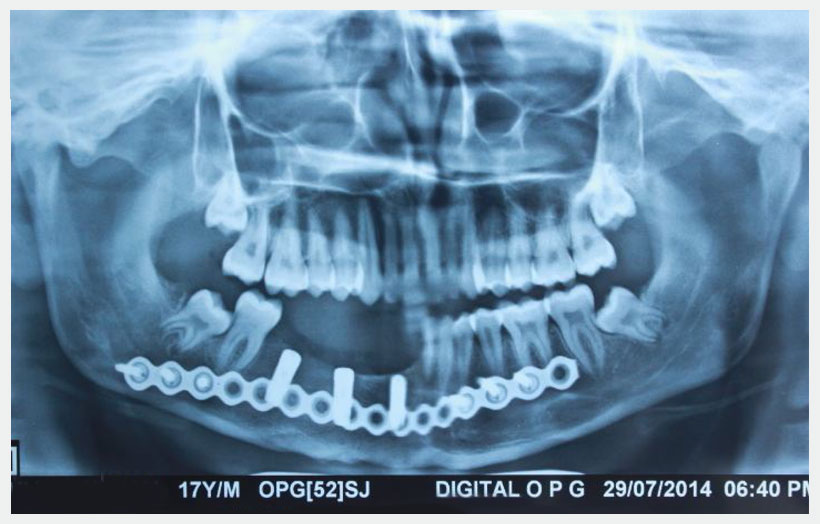

18 year old male patient came with chief complain of Swelling over Rt side of lower jaw. He was diagnosed as Benign Ossifying fibroma. Surgery was made in Feb 2013 for excision of lesion and reconstruction using Iliac crest cortico-cancellous bone graft from right side. Bone graft fixed to the defect using a reconstruction plate. After 1 year we can see adequate bone formation at the defect side. He is planed for replacement of missing teeth using 3 Alpha Dent 5×13 mm classic implants.